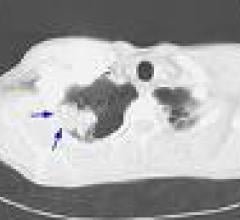

August 21, 2009 - A study published in the August 2009 edition of the Journal of Thoracic Oncology found that non-small cell lung cancer (NSCLC) patients could be more accurately staged at diagnosis by taking into account the level of visceral pleura invasion (VPI). VPI is the extension of a tumor beyond the elastic layer of the visceral pleura.